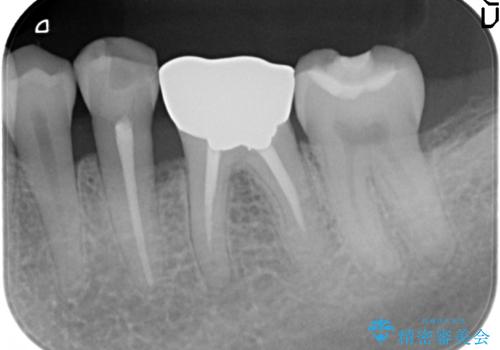

臼歯 咬合の再構成

- 20年前に治療した銀歯が壊れ、審美的な修復を希望され来院されました。

銀歯・虫歯を除去し、ジルコニアを咬合再構成を行います。

- 66万円(仮歯・ジルコニアクラウン×6)費用は治療当時の料金となります

ジルコニアクラウンは補綴治療を行う上で、審美的かつ強度を備えたクラウンです。